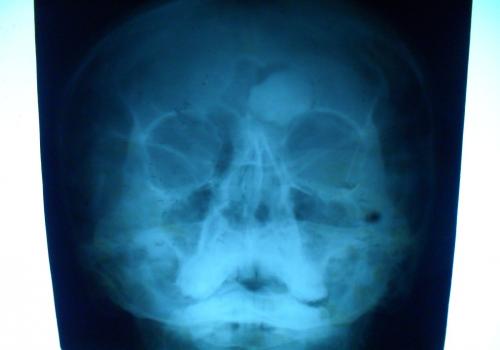

Остеома

Различают губчатую остеому, остеому, состоящую из коркового и губчатого вещества, и остеому из сплошного компактного вещества. Первые два вида наблюдаются на длинных трубчатых костях, компактные остеомы поражают плоские кости черепа.

- остеома всегда солитарна, - форма шаровидная, шиповидная, - опухоль сидит на кости на широкой правильной ножке, - корковый слой при остеоме не нарушен. - контуры гладкие, ровные, - губчатая сеть кости и опухоли непрерывно переходит друг в друга. |

- округлая, шаровидная или яйцевидная форма, - опухоль дает гомогенную бесструктурную тень. |